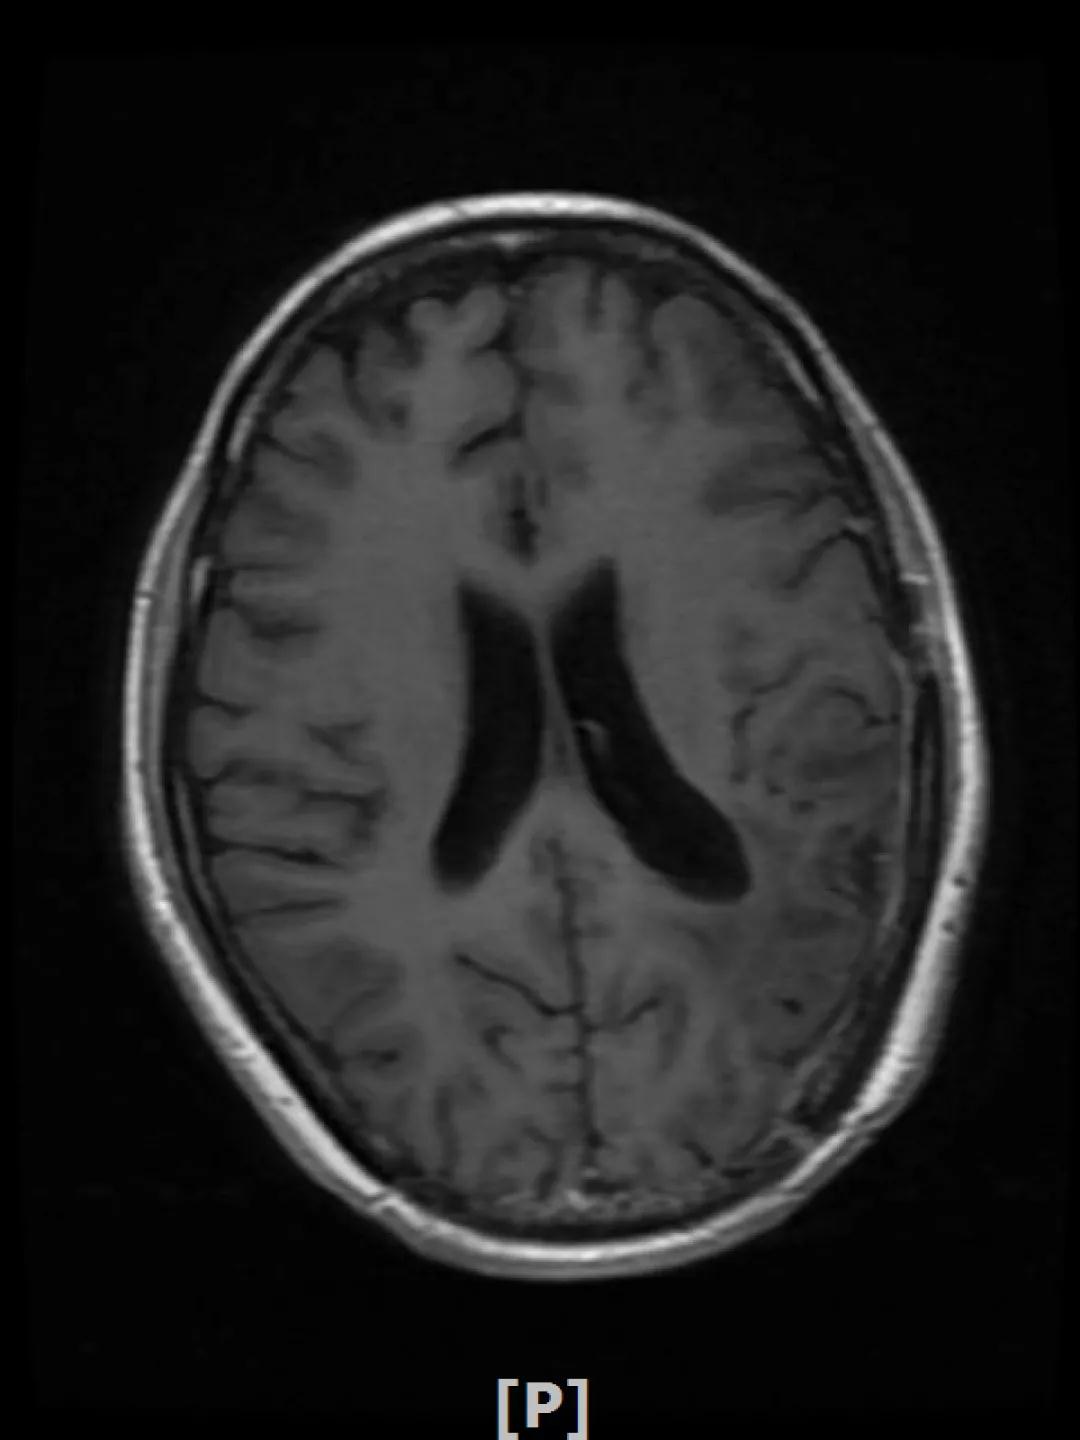

6.病情第5次进展:2020年5年患者头痛等症状进一步加重

头颅增强MR:左侧顶叶皮层区见不规则片状T1WI低信号、T2WI高信号影,病灶大部信号接近脑脊液,增强后无强化,其边缘见结节样明显强化影,平扫近似等信号,大小约12x12mm,较2020-02-11MR老片略增大,左侧脑室三角区不均扩大;右侧颞叶-丘脑区见结节样T1WI等低信号、T2WI不均匀高低混杂信号影,增强后不均匀明显强化,大小约24x23x26mm,较前片增大,似见累及胼胝体压部;两侧半卵圆区、侧脑室旁、基底节区及右侧丘脑、颞叶见融合团片状T1WI低信号、T2WI及Flair高信号影,增强后未见明显强化,较前片相仿;余脑室、脑池、脑沟大小形态可,中线结构向左偏移。左侧乳突区见T2WI高信号影充填。

颅脑转移瘤治疗后观

左顶叶强化结节、右侧颞叶-丘脑区结节影:较前片增大

幕上脑白质融合异常信号:符合放疗后改变

患者四线解救治疗的PFS为5个月。2020年6月改用T-DM1方案治疗(恩美曲妥珠单抗,160mg,21d重复),同时改用依西美坦(25mg,qd)

患者头痛等症状明显好转,病灶持续缩小,继续定期复查。